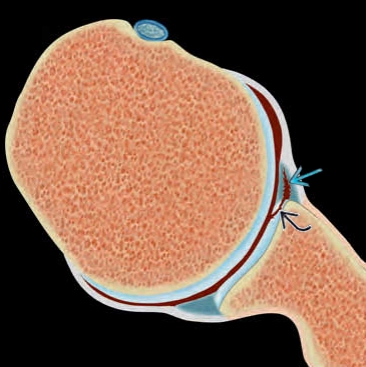

Tổn thương ALPSA (Anterior Labrum Periosteal Sleeve Avulsion)